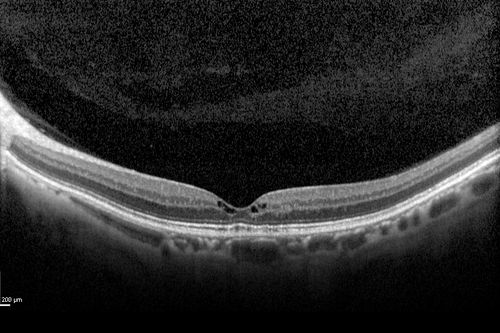

63-year-old woman has juxtafoveal retinal telangiectasis in both eyes.  She notices her vision a little worse with more distortion and change over the last six months.

VISUAL ACUITY:  OD 20/40,  OS 20/40.